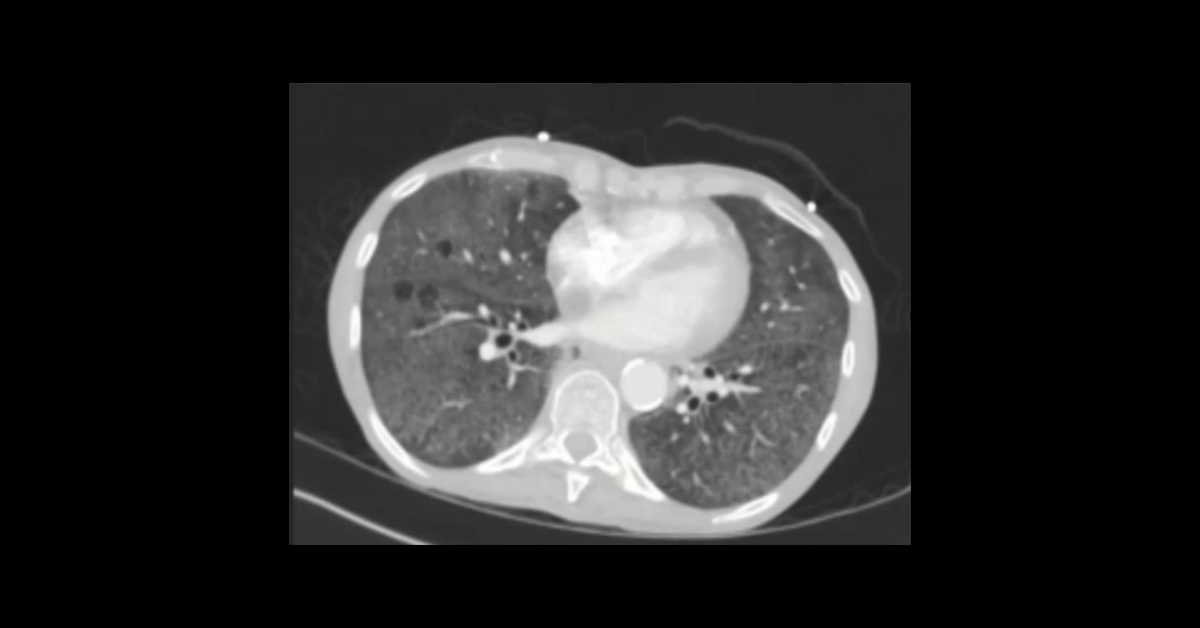

Course Overview

A collection of obstetric ultrasound studies presented in cine and screen shot formats, with initial presentation of each case enabling participants to render their own diagnoses followed by detailed discussion of each case.